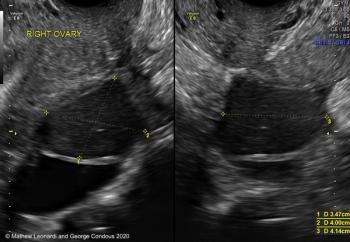

In this case, there is a fixed ovary posteriorly and subtle hypoechoic nodule posterior to the uterus at the level of the internal cervical os, suggesting of deep endometriosis of the torus uterinus.